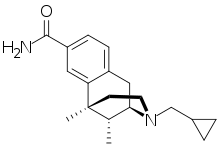

Uncategorized opioids

- ADL-5859

- Alimadol

- Amentoflavone

- Anilopam +HCl

- Asimadoline

- Cyproterone acetate

- FE 200665

- Fedotozine

- HZ-2

- Kolokol-1

- Matrine

- MCOPPB

- Menthol

- MT-7716

- Nalfurafine

- Nalorphine

- Nalorphine dinicotinate

- PZM21

- Proglumide

- Ro65-6570

- SoRI-9409

- Spiradoline

- SR-8993

- SR-16435

Structures

| Uncategorized opioids | ||||

|---|---|---|---|---|

|

|

| ||

|

|

| ||

|

Nalodeine Nalodeine |

|

| |

|

||||